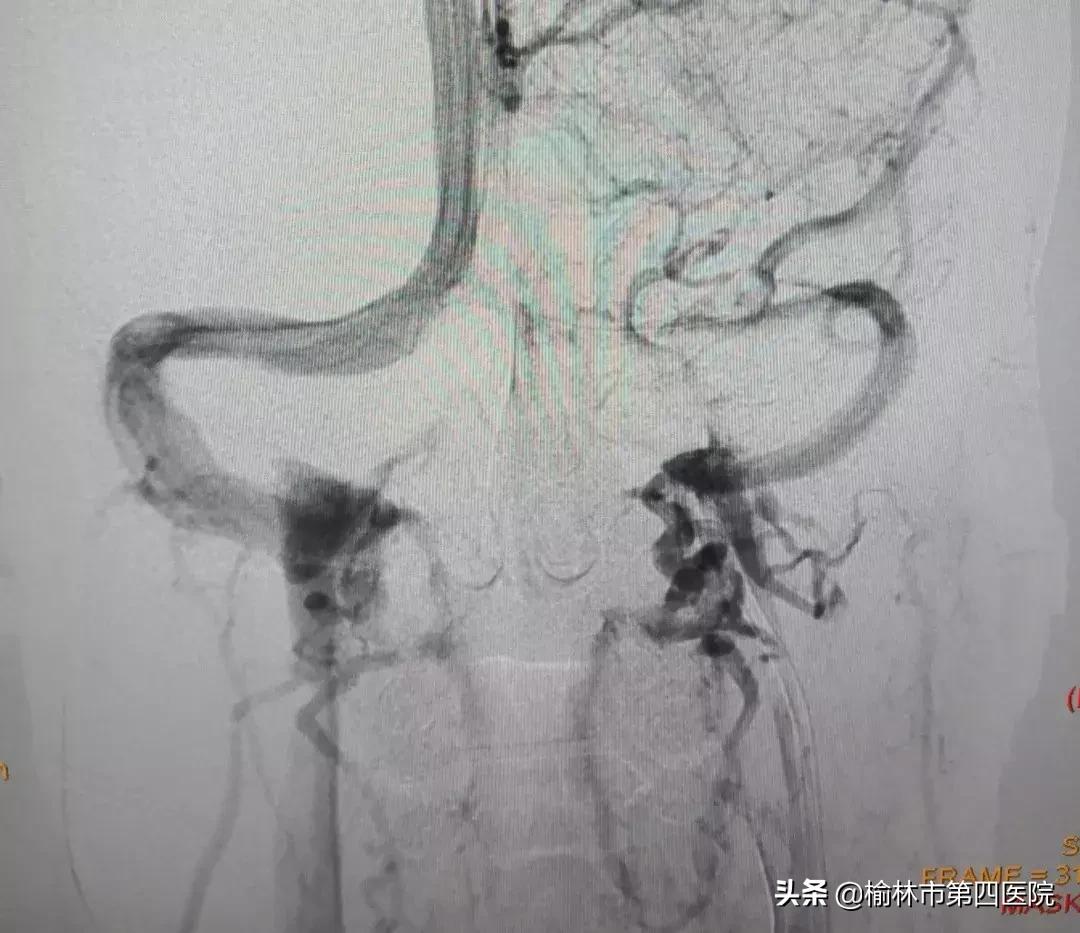

患者青年男性,5年前因病毒性脑炎治疗后持续头痛、头闷,症状时轻时重,一个月前“感冒”后出现头痛、头闷进行性加重,伴视物模糊,四处求医未果。后慕名就诊于榆林市星元医院,入院查体、各项化验、头颅MRI均未见明显异常,诊断性腰椎穿刺显示高颅压,眼底检查视乳头水肿。神经内一科常文利主任、李强主治医师凭借丰富的临床经验,考虑病因为颅内静脉系统疾病,遂行头颅MRV及全脑血管造影(DSA)示:左侧横窦长段重度狭窄。

经过认真细致的准备,采取静脉麻醉下经股静脉入路的方案,术中股动脉造影导管和股静脉导引导管*管双**齐下,最终应用球囊序贯扩张左侧横窦狭窄段,因考虑到患者年龄较小,扩张后狭窄改善,故未予植入支架,为患者疏通了血流通道。